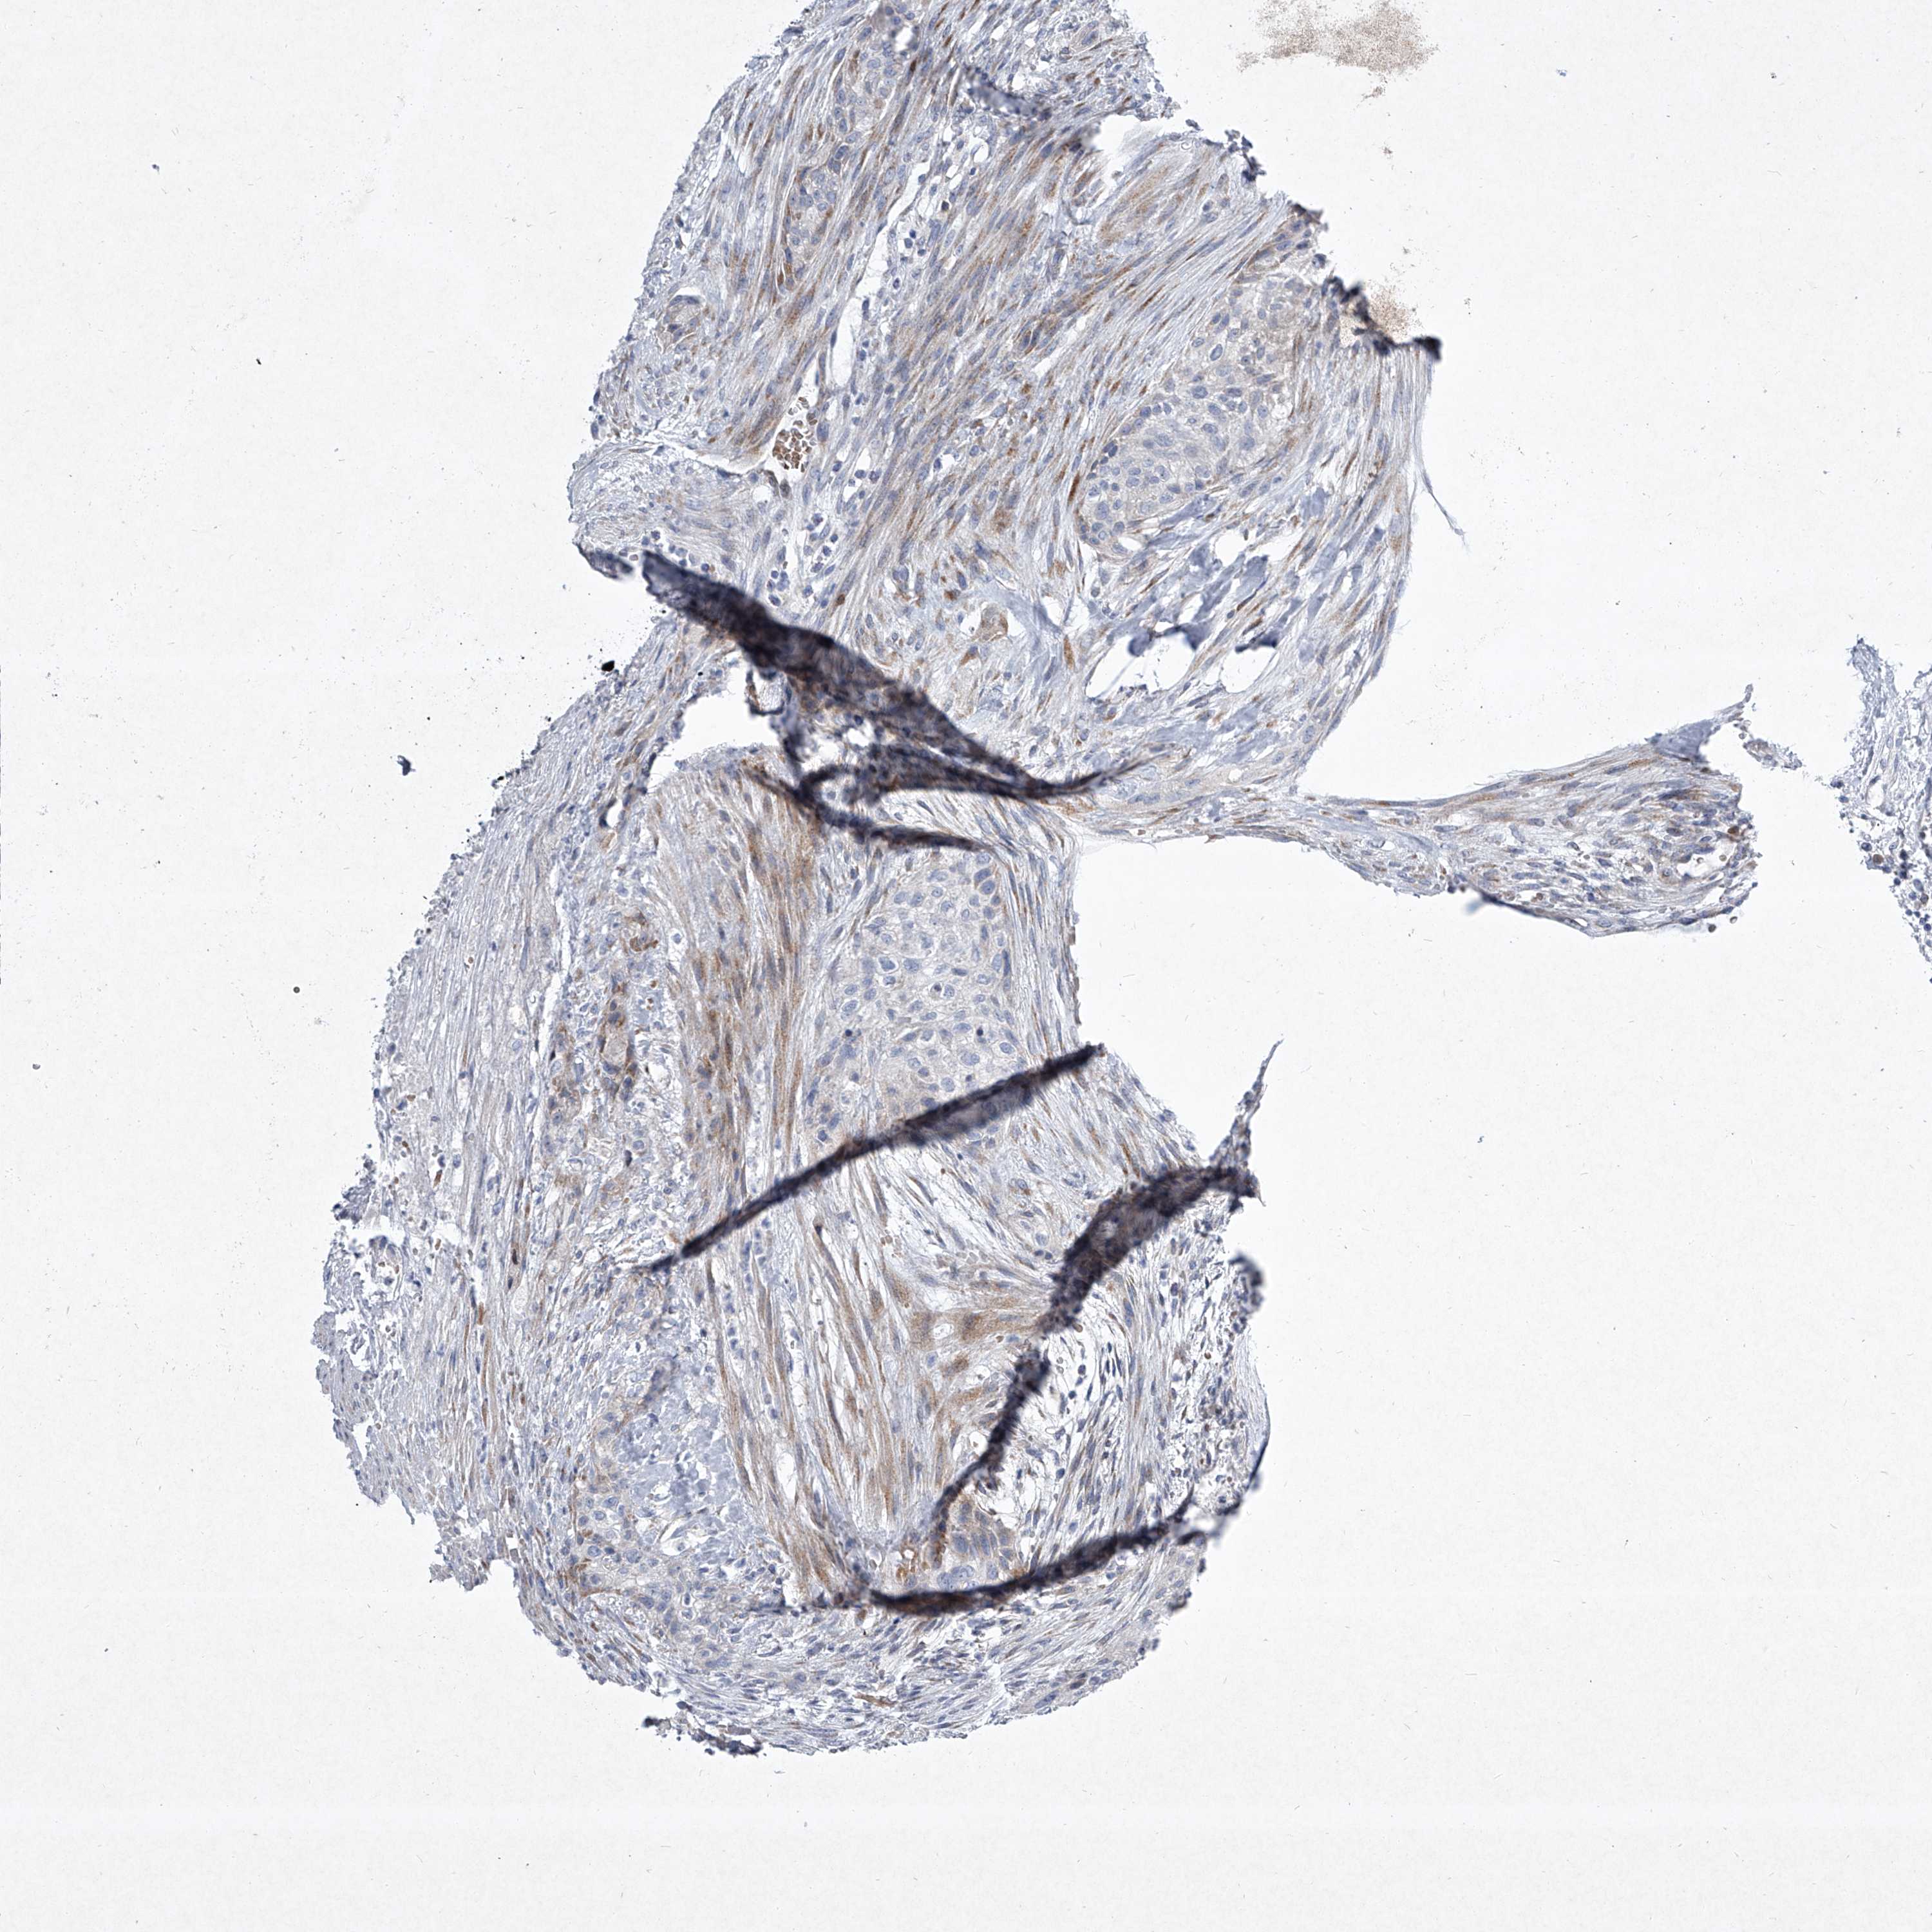

UROTHELIAL CANCER - Protein expressioni

A mouse-over function shows sample information and annotation data. Click on an image to view it in a full screen mode. Samples can be filtered based on level of antibody staining by selecting one or several of the following categories: high, medium, low and not detected. The assay and annotation is described here.

Note that samples used for immunohistochemistry by the Human Protein Atlas do not correspond to samples in the TCGA dataset.

Antibody stainingi

Antibody staining in the annotated cell types in the current human tissue is reported as not detected, low, medium, or high, based on conventional immunohistochemistry profiling in selected tissues. This score is based on the combination of the staining intensity and fraction of stained cells.

Each image is clickable and will lead to virtual microscopy that enables deeper exploration of all samples and also displays staining intensity scores, fraction scores and subcellular localization as well as patient and tissue information for each sample.

Antibody CAB034059

Staining

High

Medium

Low

Not detected

Intensity

Strong

Moderate

Weak

Negative

Quantity

>75%

75%-25%

<25%

None

Location

Nuclear

Cytoplasmic/membranous

Cytoplasmic/membranous,nuclear

Urothelial carcinoma, Low grade

Urothelial carcinoma, High grade